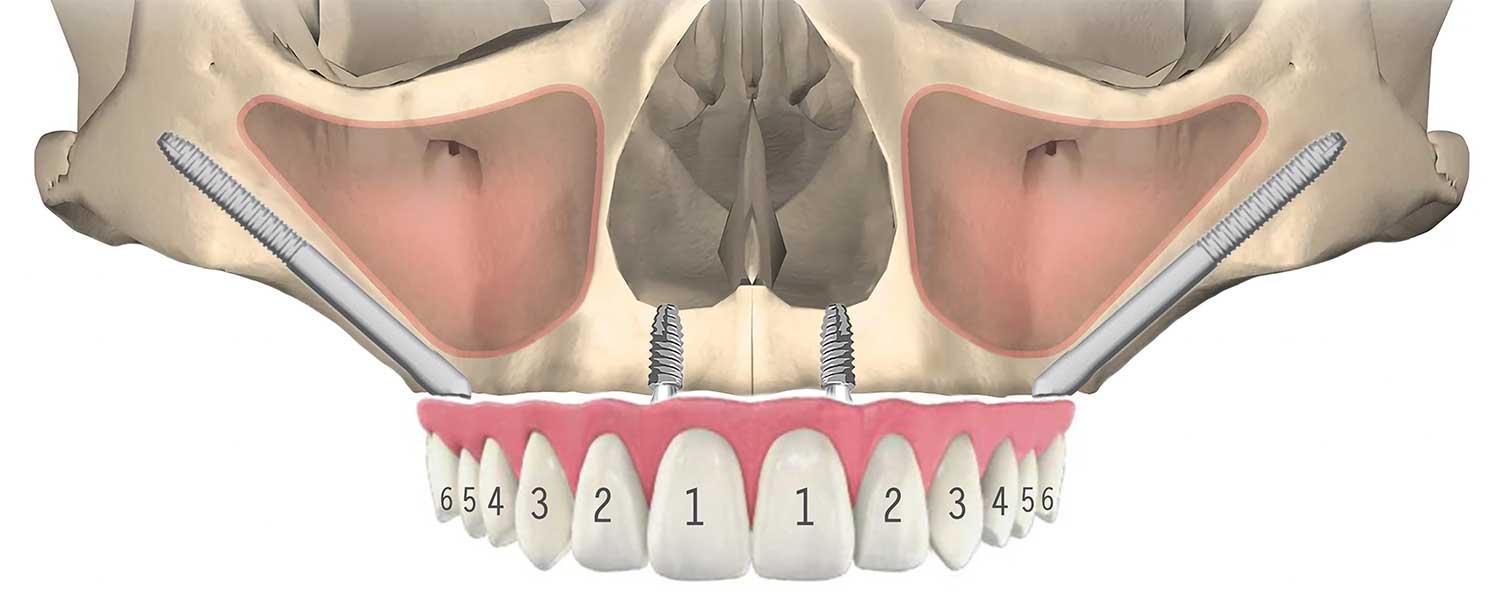

ザイゴマインプラントとは、上顎の骨が著しく吸収して通常のインプラントができない場合や、上顎洞が大きく張り出している場合に、頬骨(Zygomatic bone)を支えとして埋入する長さのある特殊なインプラントです。

通常のインプラントは一般的に6mmから18mm位ですが、ザイゴマインプラントは30mmから52.5mm(NobelBiocare)の長さがあります。

骨が無い為に、点線(⋯⋯⋯)の位置にインプラントを入れる事が出来ない(オールオン4が出来ない)場合(右側)、ザイゴマインプラントを頬骨に入れる事で、問題を解決する事が出来ます。それにより、手術と同時に仮歯を入れる事が可能となります。

前方は通常のインプラント、後方にザイゴマインプラントを用い上部構造を支える方法を、一般的にオールオンフォーハイブリッドと呼びます。

03All-on-4 Double Zygoma

前方、後方にザイゴマインプラントを用い上部構造を支える方法を、一般的にオールオンフォーダブルザイゴマやクアッドザイゴマと呼びます。上顎骨が大きく萎縮してしまったケースに対し、ザイゴマインプラントのみを用いる非常に難易度が高い治療法です。